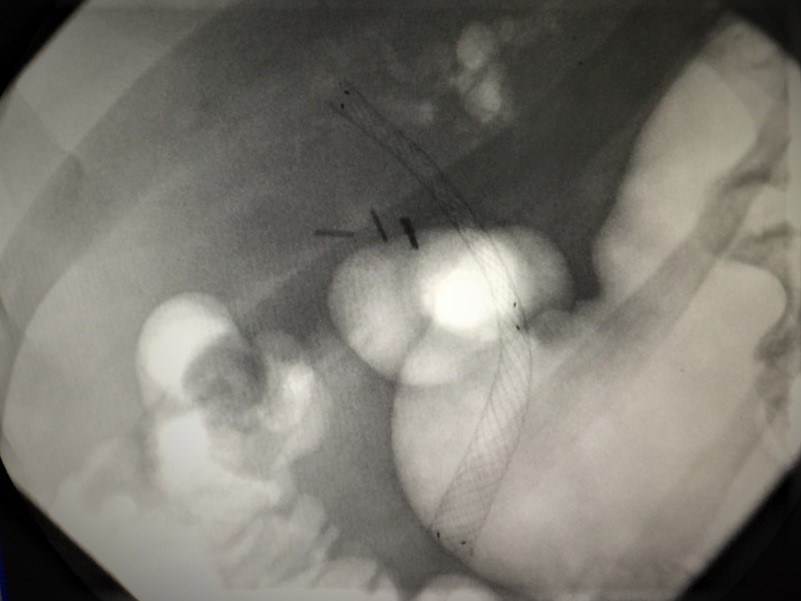

Recent echipa de endochirurgi formată din Cotoneţ Alic şi Bodrug Roman a realizat una din cele mai dificile protezări ale ductului hepatic comun cu proteza metalică autoexpandabilă. Un caz depăşit de neoplasm perihilar hepatic, la care mai multe tentative endoscopice şi intervenţii chirurgicale tradiţionale au eşuat. Anterior, la prima şedinţă endoscopică s-a reuşit canalizarea ductului hepatic comun şi instalarea unei proteze biliare din palstic. Starea pacientului s-a ameliorat, iar după două cure de chimioterapie la o adoua intervenţie endoscopică, proteza din plastic a fost înlocuită cu una metalică autoexpandabilă. Astfel de proteze asigură un flux biliar adecvat pe o perioadă de timp mai îndelungată.